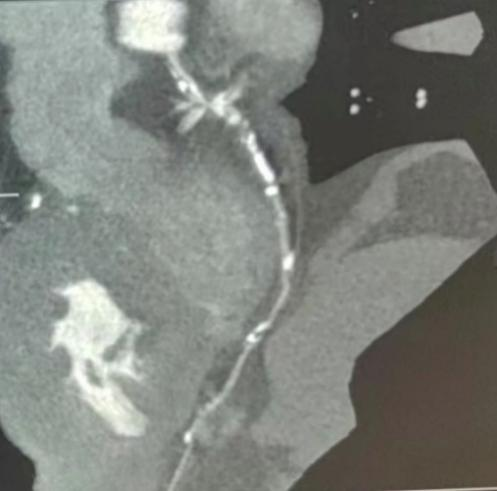

患者马先生,男性,49岁,在格尔木市人民医院常规体检时行冠脉CTA检查发现:冠装动脉呈右优势型;右冠状动脉(RCA)近、中及远段管壁钙化斑块,管腔重度狭窄;左主干管壁钙化斑块,管腔重度狭窄;左前降支管壁钙化斑块,管腔轻度狭窄;左回旋支管壁硬化斑块,管腔轻度狭窄(图2)。因当地医疗条件有限,慕名前来青海省人民医院心内科进一步诊治。

图2 冠脉CTA检查结果 :

a. 右冠;b. 前降支